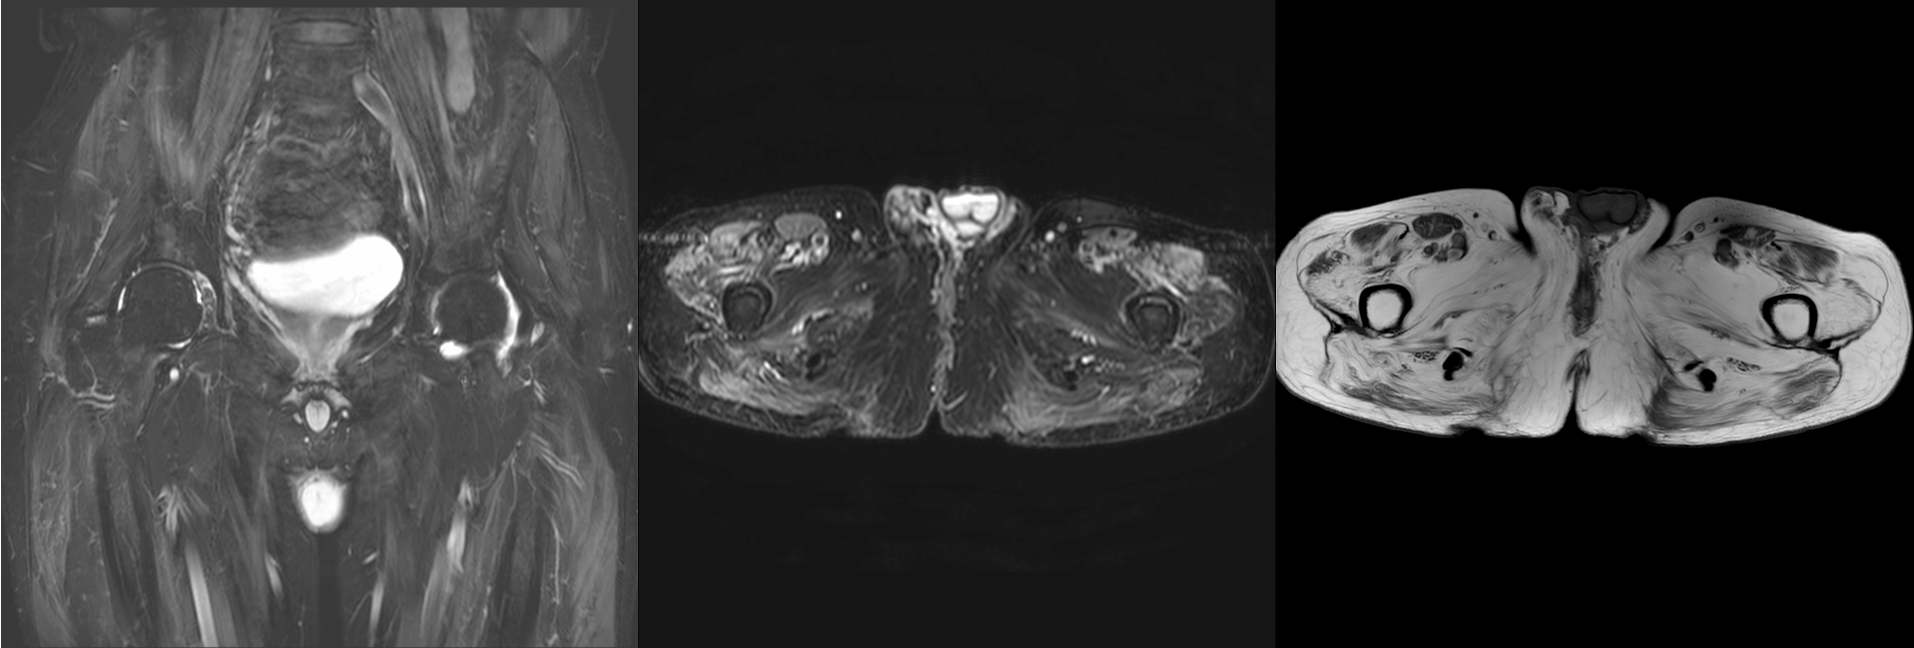

Case 61: Dermatomyositis and the Myositis Protocol MRI

55-years old with dermatomyositis

55-years old diagnosed to have dermatomyositis, referred for a myositis protocol MRI.